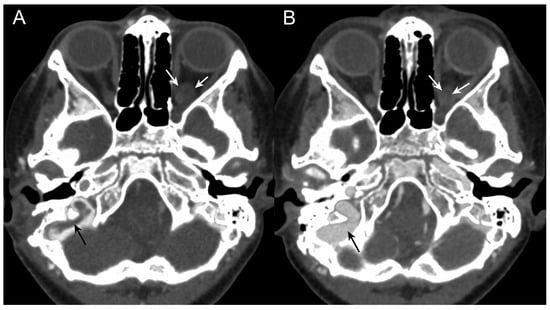

3.1. Case Report